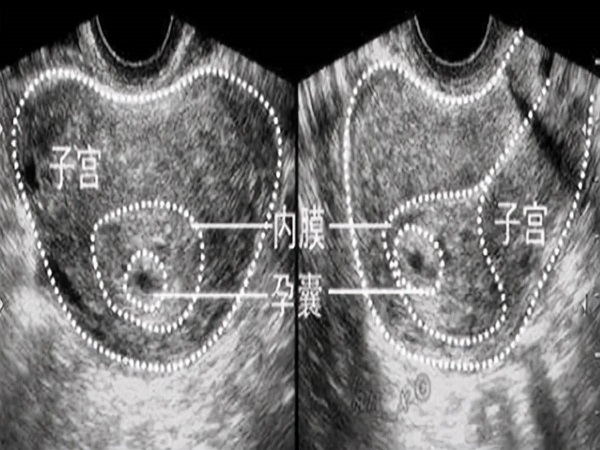

XY孕囊和XX孕囊形状大不同,长条形和圆形早已暗示胎儿性别

孕囊是受精卵分裂发育而来的小胚胎,在胎儿还没有完全形成的时候就以孕囊的形式存在,因此孕妇在前几次产检的时候都会检查孕囊的发育情况,从而判断胎儿是否在正常发育。孕..

弄清孕囊圆形和椭圆形的区别,方知哪个发育得更好

众所周知,孕囊是胚胎早期的一种形态,随着孕周的逐渐变大,孕囊的形状和大小都会发生改变,直至最后消失。孕囊的形状主要有两种一种是圆形的,另一种是椭圆形长条形的。圆..

早期孕囊形状看性别图片圆形是男孩这个说法准吗-数据对比一目了然

早期孕囊形状看性别图片圆形是男孩这个说法准吗-数据对比一目了然,是不准的,在医院或者生殖中心我们经常看到很多的准妈妈拿着B超单看了又看,还跟旁边的同来检查的孕妈一..